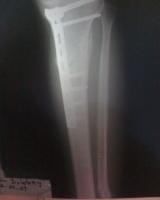

Fractura metafisiaria de tibia izquierda..

Doctor mi nombre es soy de la ciudad de Caracas Venezuela tengo 19 años de edad queria hacerle unas cuantas preguntas con respecto a mi fractura como lo indica el titulo una fractura metafisiaria de tibia izquierda el dia 01/01/09 ingrese al hospital y me indicaron que tenia que quedar internado hospitalizado durante 1 mes espere la operacion el dia 28/01/09 me operaron se me realizo una reduccion mas fijacion interna con placa lcp 4,5++ ingerto oseo en fisura de tibuia izquierda evolucione de forma satisfactoria y fui dado de alta el dia 30/01/09 acudi a control en el hospital pero devido a que me plantearon retiro de tornillo proximal, les plantie que necesitaba consultar con otros traumatologos y me indicaron que no era necesario devido a eso me retire del hospital y acudi a otro centro cree usted que sea el tipo de placa indicado el que me colocaron?.